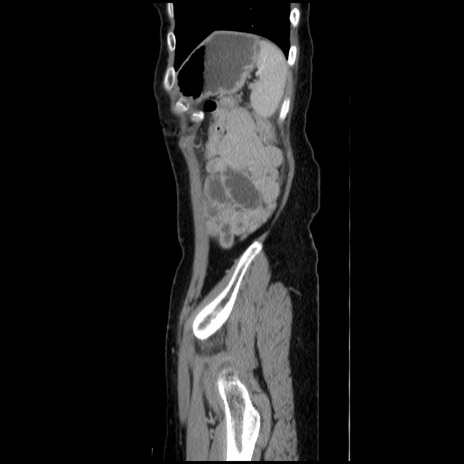

冠状断像

【症例】40歳代 女性

【主訴】上腹部痛、嘔気・嘔吐

【現病歴】約9時間前頃から急に上腹部痛、嘔気、嘔吐が出現。改善しないため救急要請。

【既往歴】子宮頚癌(広汎子宮全摘術、放射線療法)、腸閉塞

【身体所見】腹部:平坦、軟、腸雑音亢進、上腹部を中心に腹部全体に圧痛あり。

【データ】WBC 8400、CRP 0.03